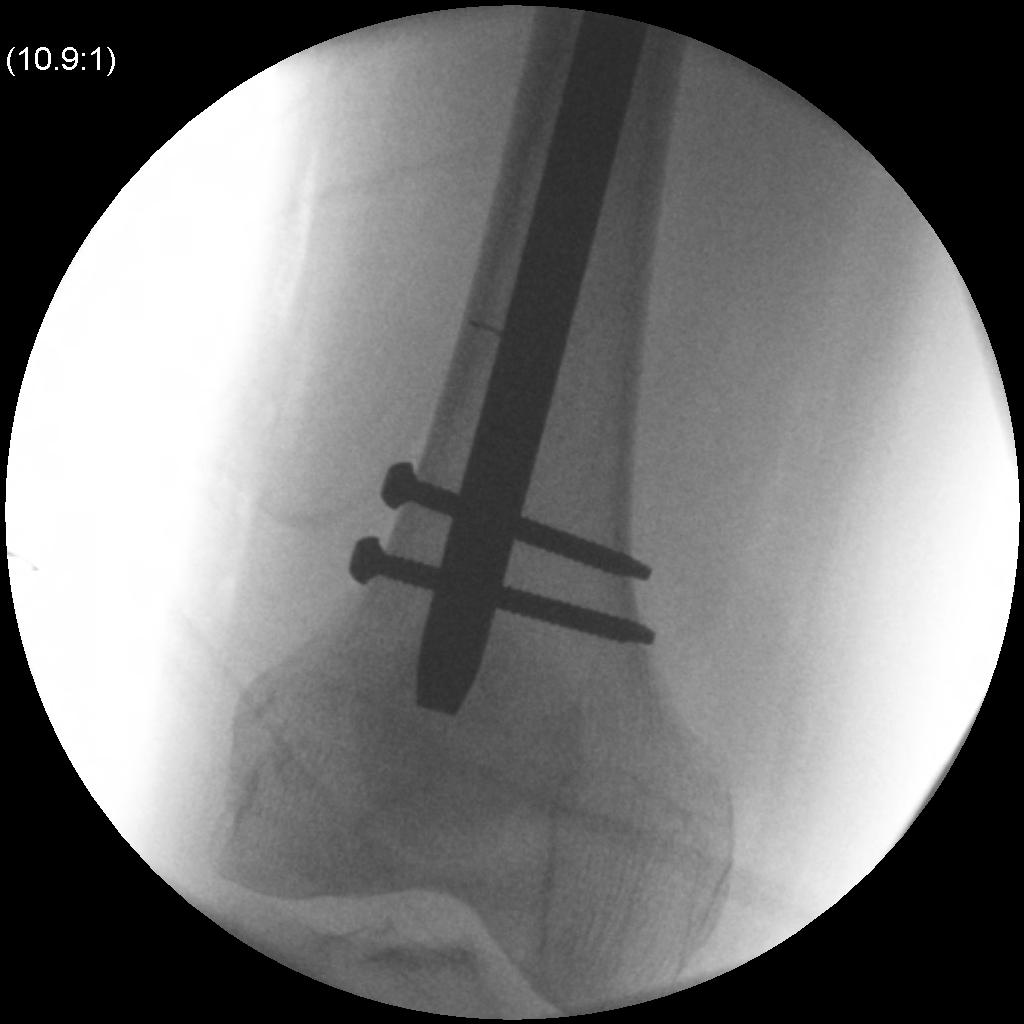

Locking

Proximal

- usually proximal locking first

- screw should purchase cortex of lesser trochanter

Distal

- straighten out other leg / lower so can obtain lateral II

- perfect circle technique

- distal locking performed